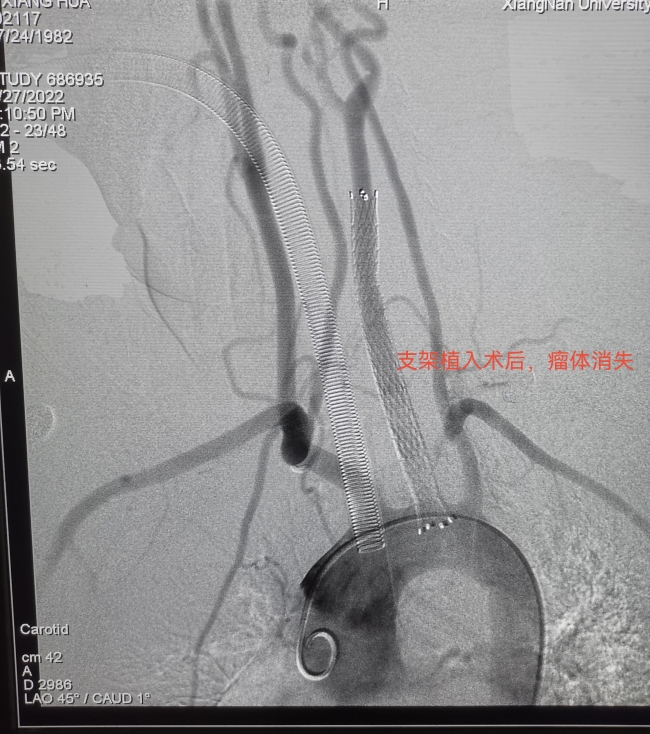

5月27日,在麻醉科协同下,李大姐在全麻下顺利接受了颈动脉瘤覆膜支架植入术。覆膜支架可以隔绝瘤体和血栓,从心脏发出的动脉血不会再冲进瘤体,瘤体破裂和血栓脱落的双重危险就此一举解除。

从麻醉中苏醒过来的李大姐感慨:“真没想到,我才睡了一觉,瘤子就消失了,感觉像做了一场梦。”手术第二天,李大姐已经恢复得行动自如。她高兴地对家人说:“家里忙,你们回家照顾孩子,我现在能够自己照顾自己了。”